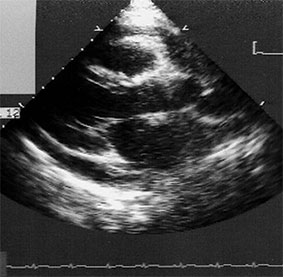

Épanchement péricardique

Le diagnostic est fait devant l’existence d’un simple décollement des deux feuillets péricardiques ou d’un épanchement péricardique qui apparaît sous la forme d’un espace clair vide d’écho (cf. fig. 20.2 et fig. 20.3). L’échocardiographie apprécie l’abondance, la topographie et la tolérance hémodynamique de l’épanchement péricardique et confirme le diagnostic d’une éventuelle tamponnade.

Fig. 20.2. Échographie d’un épanchement péricardique de moyenne abondance.